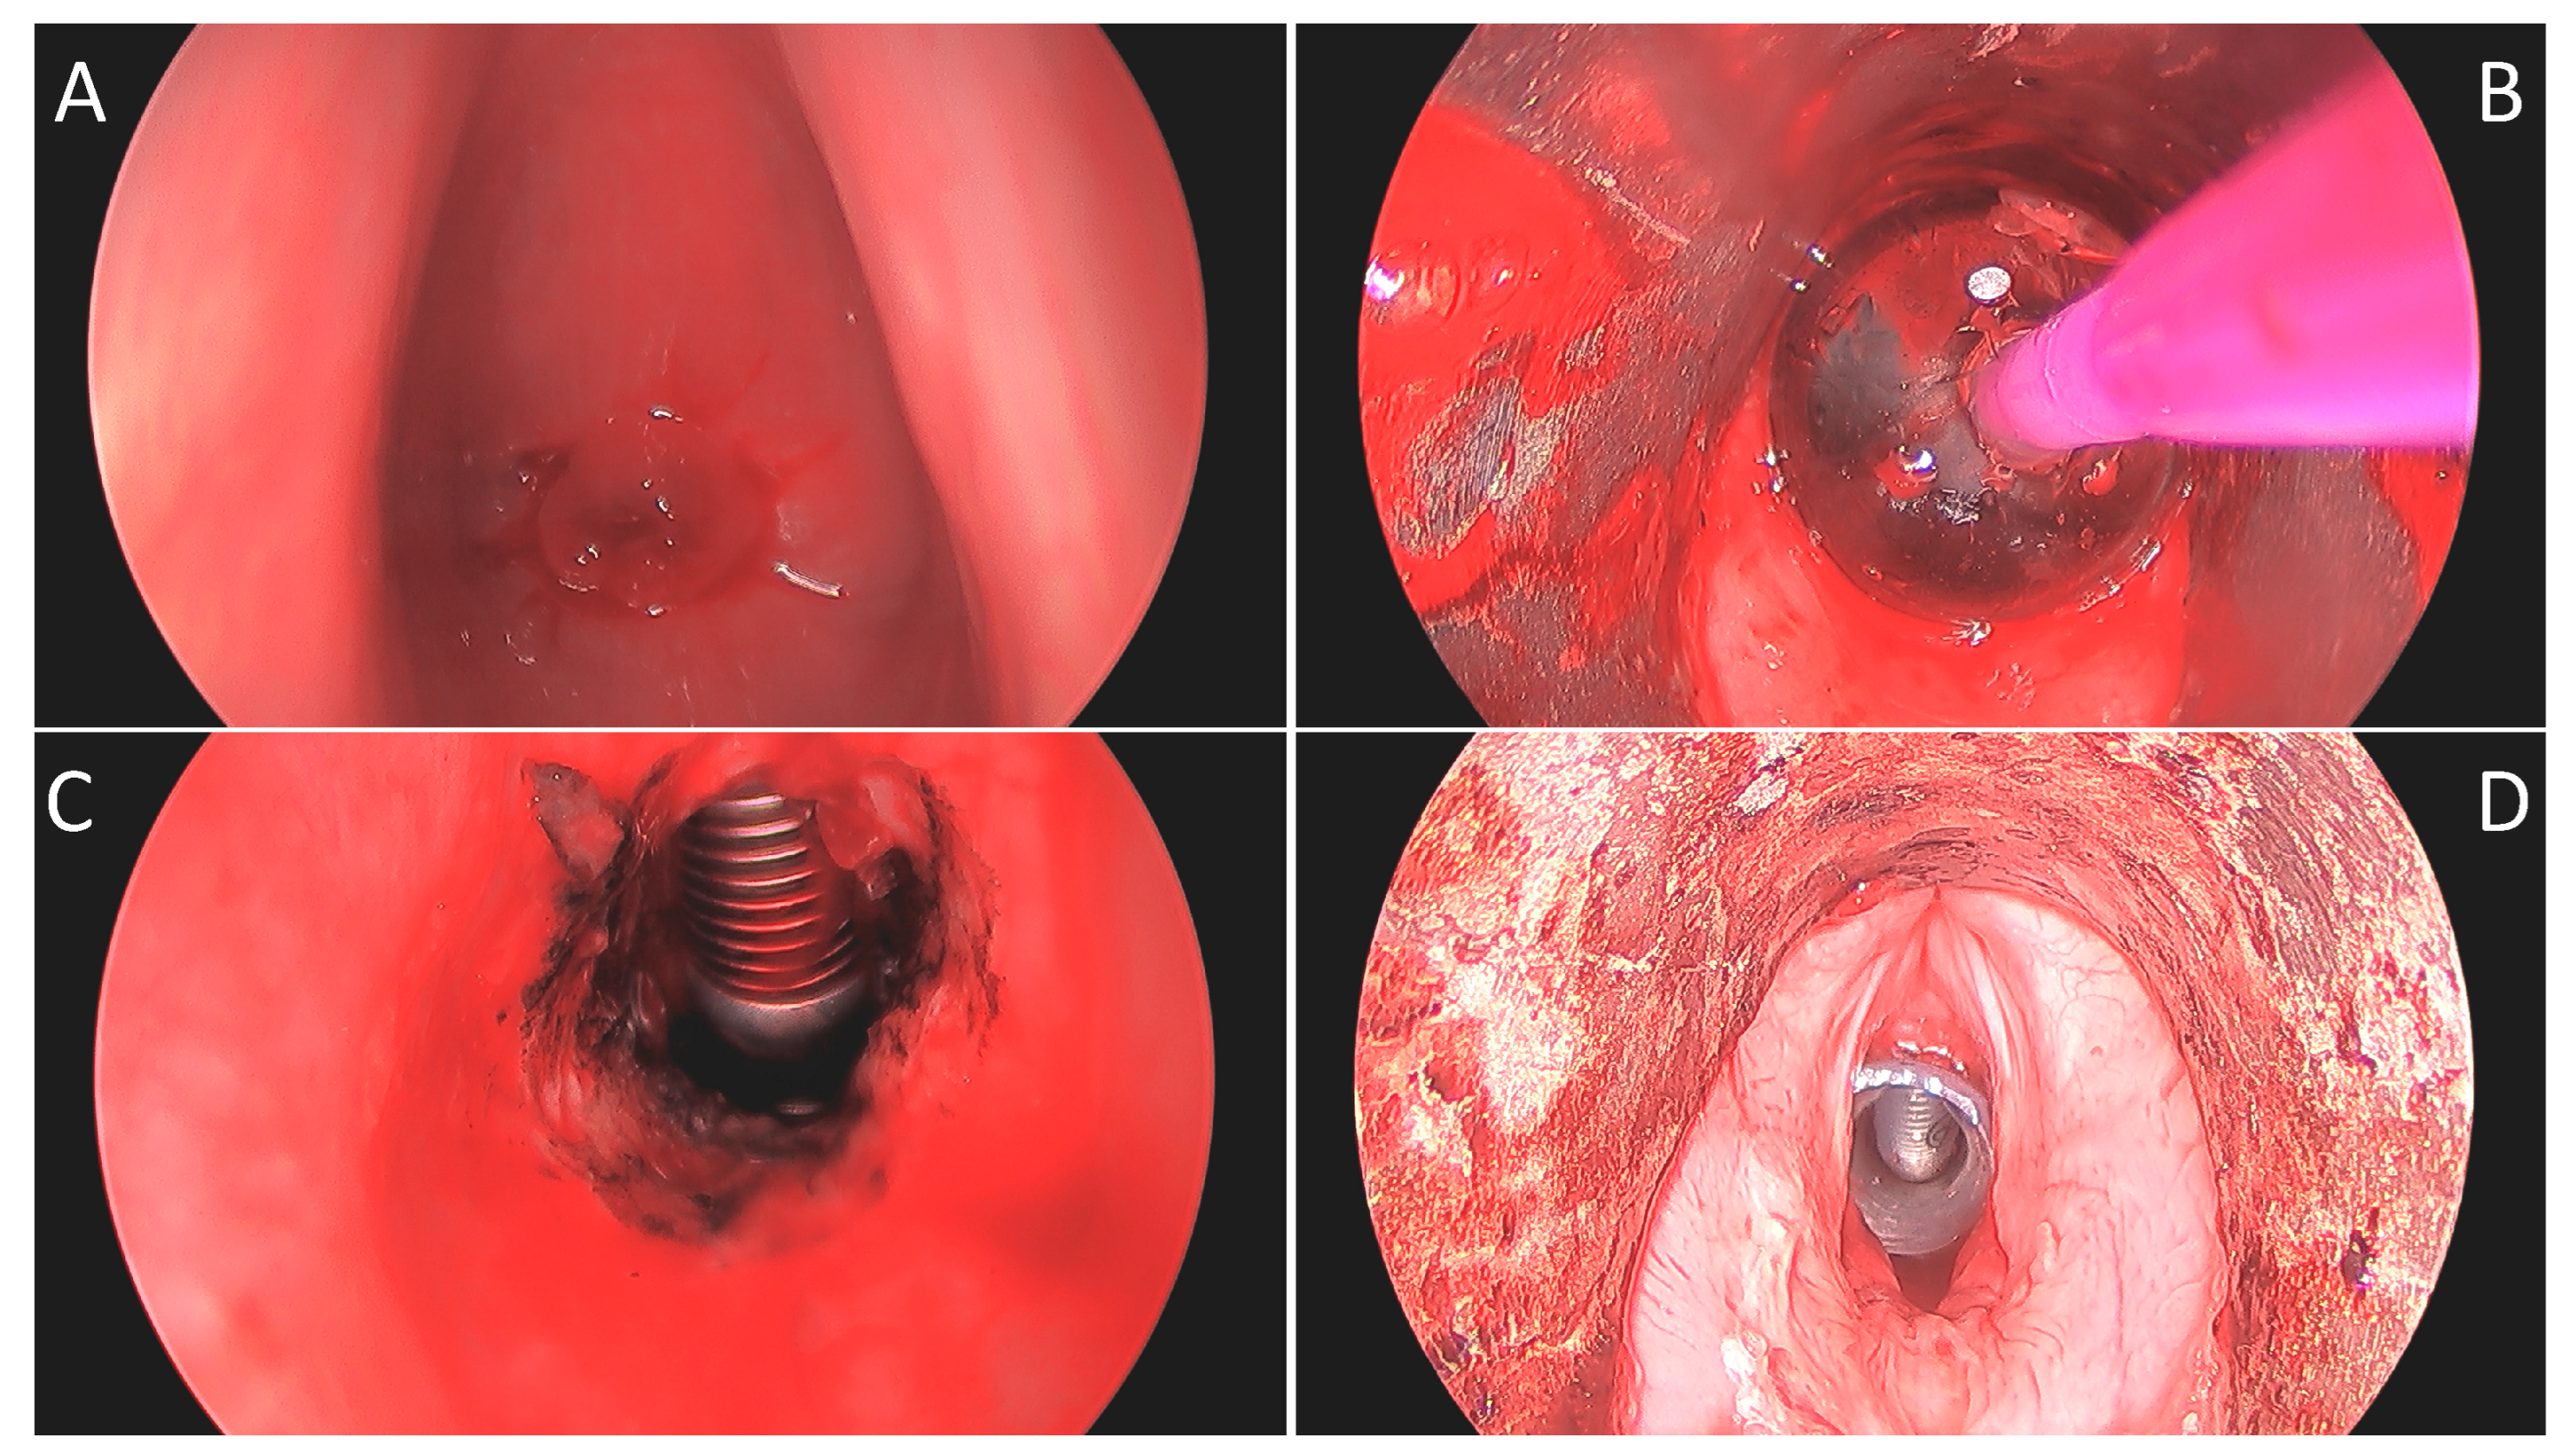

Figure 1.

Intraoperative 0° telescopic images of patient “C”: (A) View through vocal folds with stenosis apex 16 mm from the superior surface of the vocal fold with anterior extent just inferior to Broyles ligament. (B) Following KTP ablation and balloon dilation to 15 mm. (C) Post-dilation view of 1.5 cm length stenosis and laser tube below. (D) After placement of a 13 mm diameter T-tube with a proximal limb of 11 mm.

Once the distal airway was entered, the residual stenosis was widened circumferentially with additional laser ablation and dilated with CRE balloon dilators (Boston Scientific, Marlborough, MA, USA) to between 12 and 15 mm (Figure 1B). A Montgomery Safe-T-Tube (Boston Medical Products, Shrewsbury, MA) was, then, trimmed appropriately and placed to span the stenotic region, terminating cranially just inferior to the infraglottis (Figure 1D). For the fifth case in the series, a custom T-tube (Hood Medical, Pembroke, MA, USA) was fashioned based on preoperative imaging. Placement of the T-tube was completed by a variety of techniques.